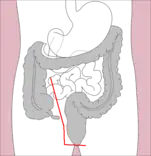

- Right hemicolectomy and left hemicolectomy refer to the resection of the ascending colon (right) and the descending colon (left), respectively. When part of the transverse colon is also resected, it may be referred to as an extended hemicolectomy.[5]

Right hemicolectomy

Right hemicolectomy Right extended hemicolectomy

Right extended hemicolectomy Left hemicolectomy

Left hemicolectomy Extended left hemicolectomy

Extended left hemicolectomy - Transverse colectomy is also possible, though uncommon.

- Sigmoidectomy is a resection of the sigmoid colon, sometimes including part or all of the rectum (proctosigmoidectomy). When a sigmoidectomy is followed by terminal colostomy and closure of the rectal stump, it is called a Hartmann operation; this is usually done out of impossibility to perform a "double-barrel" or Mikulicz colostomy, which is preferred because it makes "takedown" (reoperation to restore normal intestinal continuity by means of an anastomosis) considerably easier.